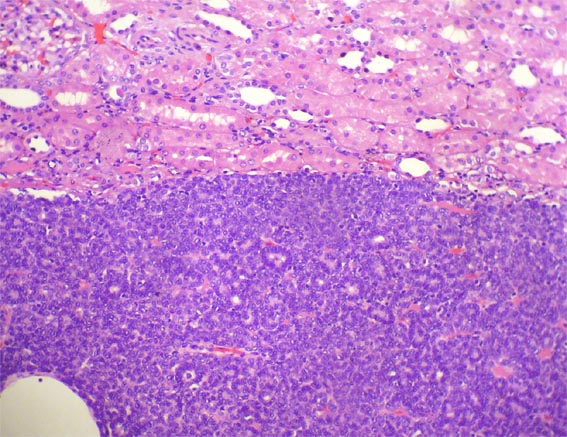

Hombre de 41 años de edad en quien

se encuentra, como hallazgo incidental, una masa de 4,2 x 4,0 x 4,0 cm

en el polo superior del riñón derecho. La masa se reseca

por nefrectomía parcial.

Observe la histología:

Figura 1.

H&E, X100.